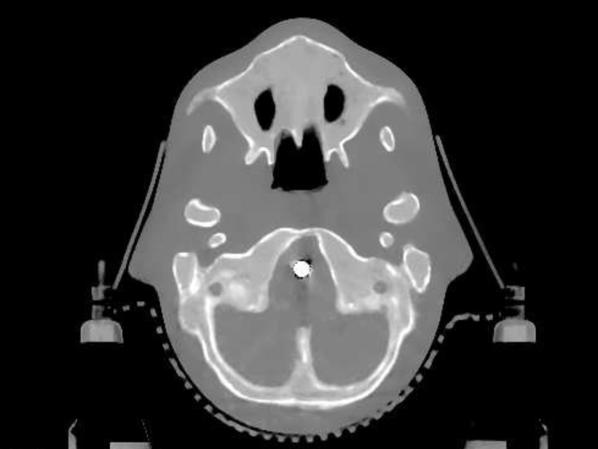

4.2 Low Dose Numerical Reconstruction Test

The data we used for our numerical reconstruction test were derived from the Adult Reference Computational Phantom (ICRP Publication 110,, 2009), which is a segmented image of defined density and chemical composition to represent real tissues. To investigate the ability to image metal implants, we inserted a pair of prosthetic hip joints (marked in green) with a solid titanium pin and shell. The slices through the chest and pelvis—which are the images we selected for testing—are shown in Figure 8. The resolution is 299×137299137299\times 137.

Refer to caption

(a) Chest test image

(b) Pelvis test image

Figure 8: Experimental data used: (a) is the oracle chest electron density; and (b) is the oracle pelvis electron density; both have a with display window of [0.8,1.2]

The results from our reconstruction test are illustrated in Figure 9 and Table 3.

Figure 9: Results from electron density reconstruction test for chest and pelvis fan-beam data with display window [0.8,1.2] to aid visualisation of soft tissue and reconstruction artefacts